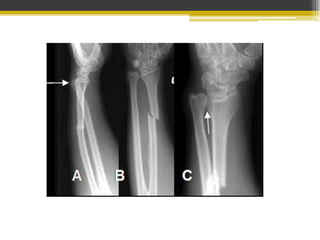

Fractura mediodiafisaria aislada, por golpe. Se trata con yeso

Fx del tercio medio del cúbito con luxación (ant, post o lat.de la

cabeza radial

Fx del tercio distal del radio con luxación de articulación radiocubital

distal.

Se reduce el radio y se fija

con una placa.

Es importante reducción completa de Fx de antebrazo ya que

unión defectuosa conlleva a pérdida de supinación, pronación…